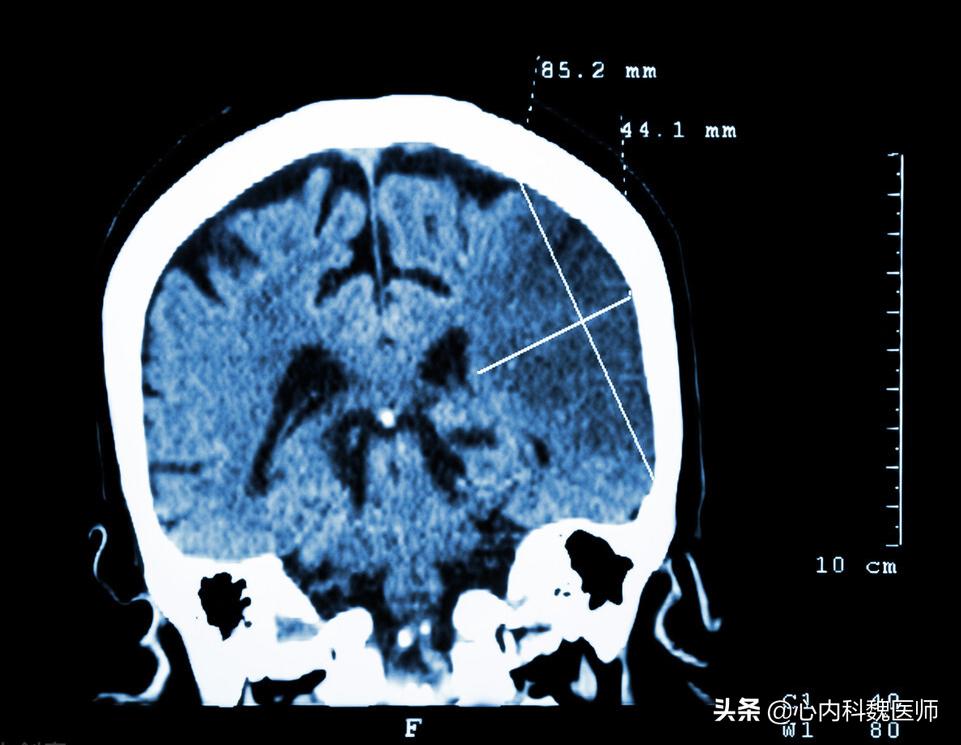

血栓缓慢地生长,脑部供血开始不足,造成头晕、嗜睡等神经系统症状,在这一阶段,医院的核磁或造影检查已经能看到明显的异常,如果及时发现,能得到有效的干预治疗。